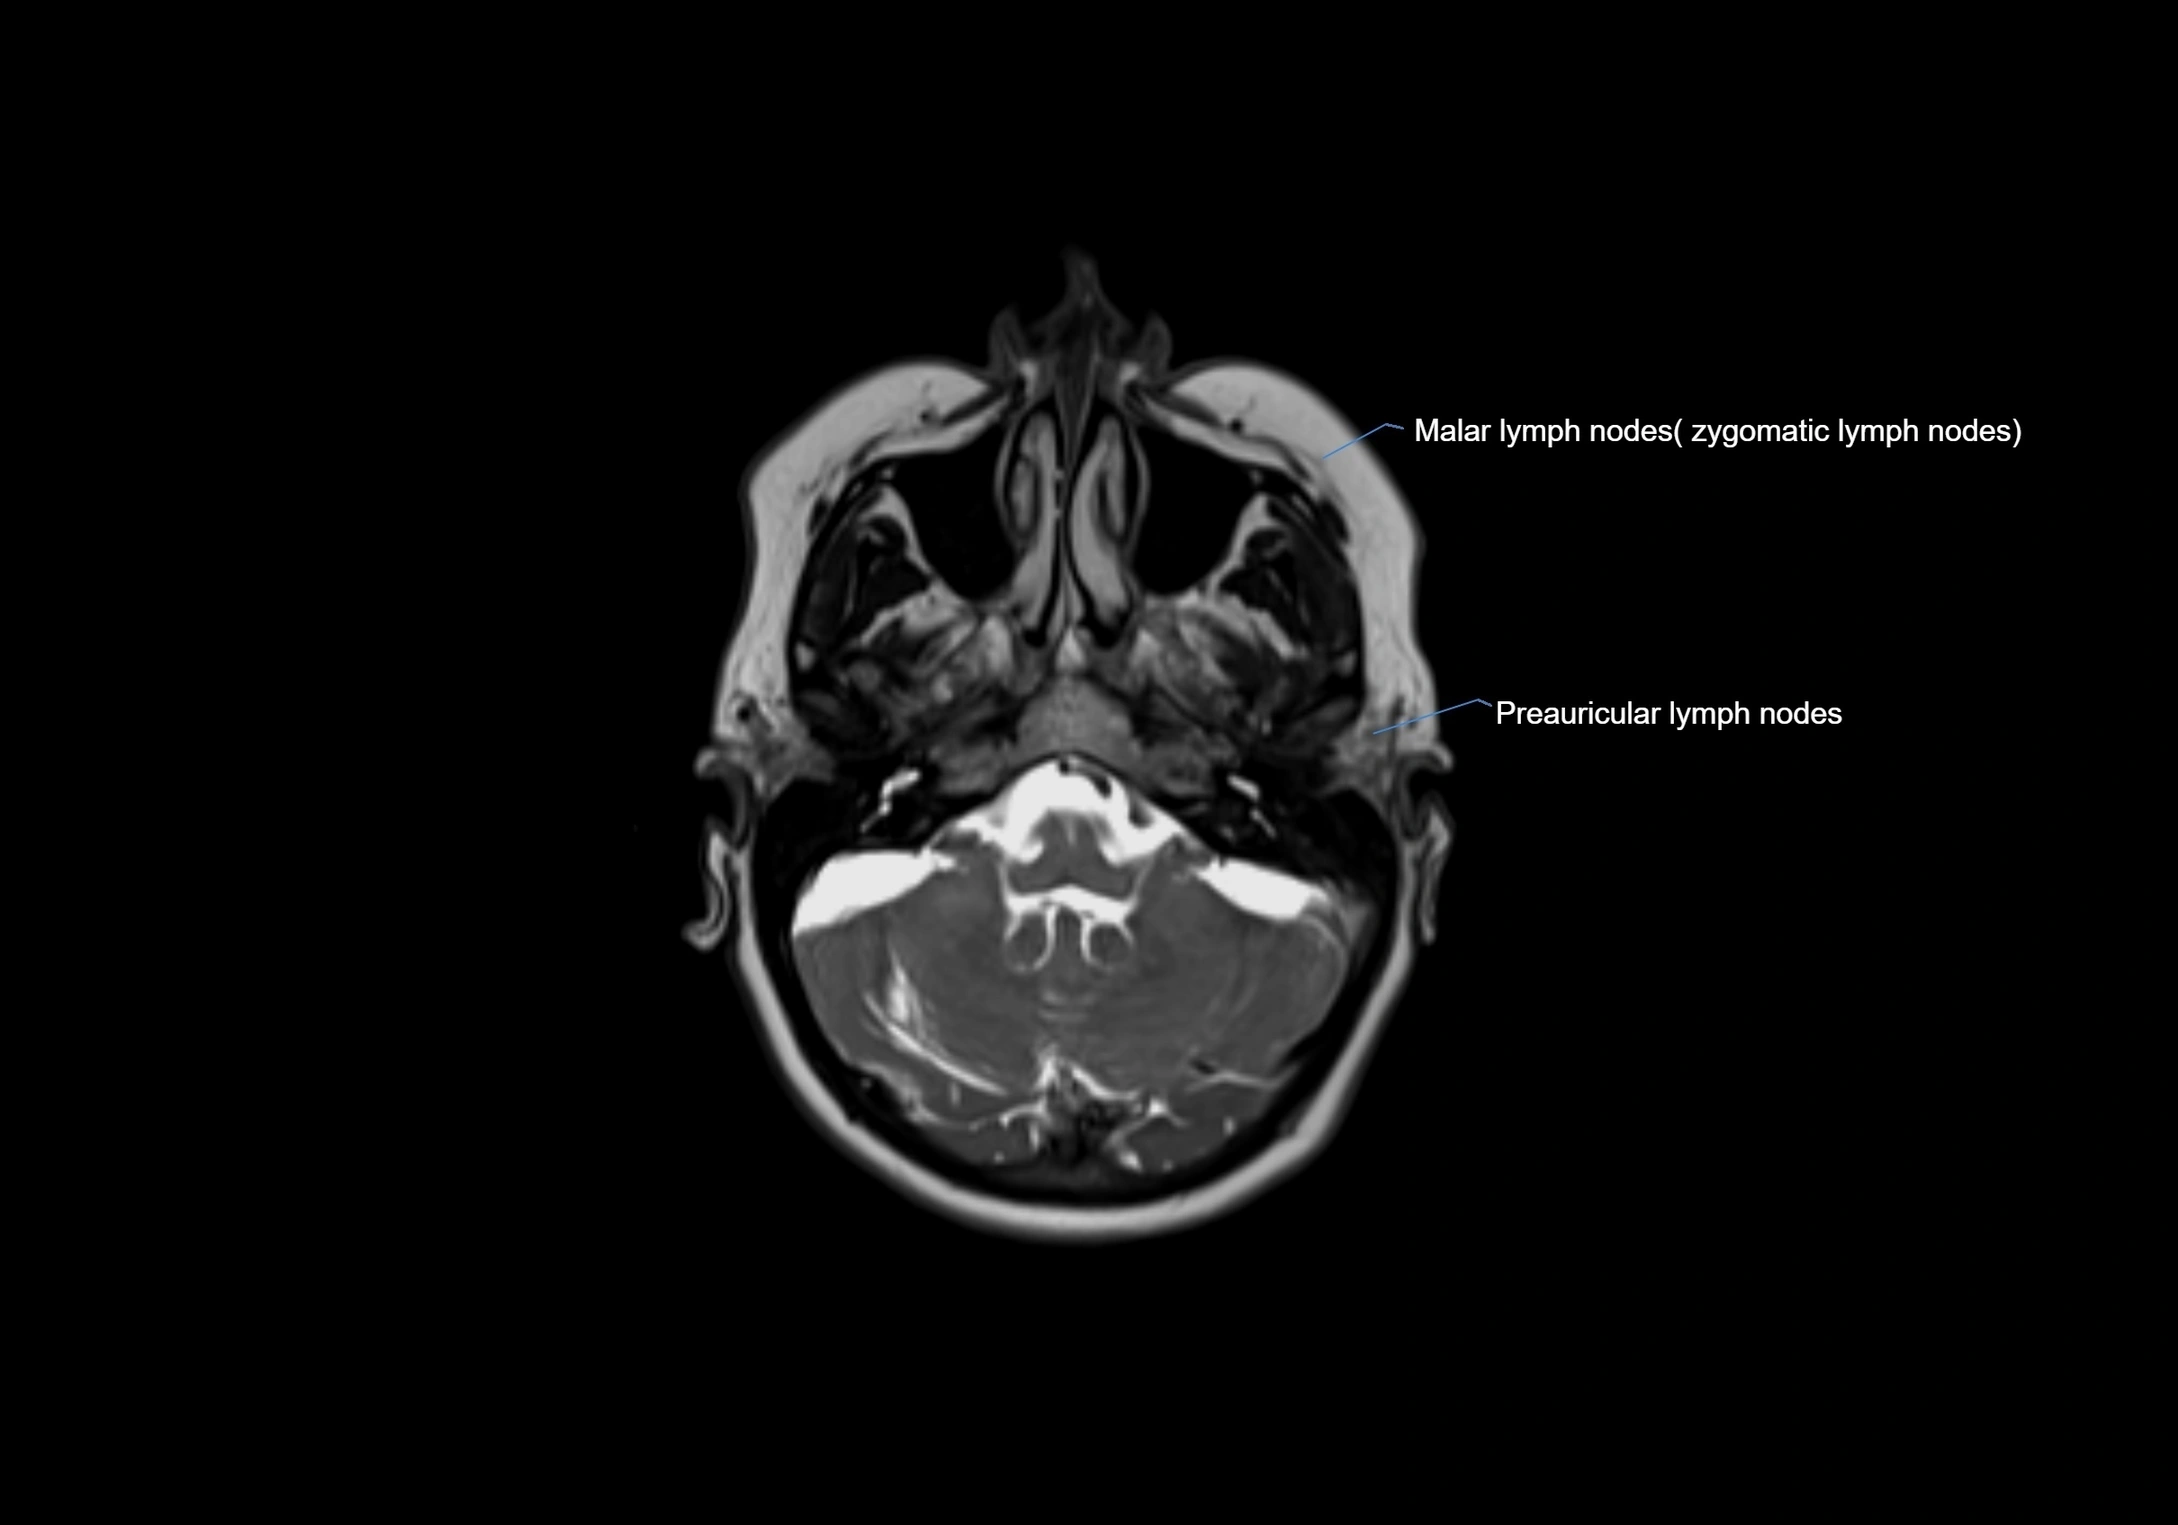

Accessory lymph nodes are small, secondary lymph nodes located along the main facial and cervical lymphatic chains, often adjacent to primary lymph nodes, such as preauricular, submandibular, or occipital nodes. They are typically less than 5 mm in diameter, embedded within subcutaneous fat or connective tissue, and may be variable in number and location. These nodes provide additional filtration and immune surveillance for lymph collected from the face, scalp, and neck regions. Accessory lymph nodes are usually non-palpable in healthy individuals but may enlarge in response to infection, inflammation, or metastasis, making them clinically significant.

Location

• Found along primary lymph node chains, including preauricular, submandibular, parotid, and occipital regions

• Embedded in subcutaneous fat or superficial fascia, often lateral or posterior to primary nodes

MRI images